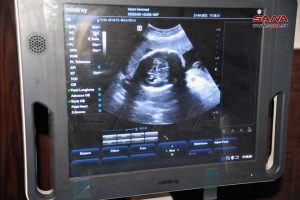

وبين الدكتور محسن في تصريح لمراسلة سانا أن عدد المراجعات للمشفى خلال الفترة نفسها بلغ 2700 مراجعة وعدد القبولات 1144 مريضة لافتاً إلى أنه تم إجراء 159 إيكو ثدي و224 صورة ماموغرافي ونقل 225 كيس دم فيما وصل عدد خدمات المخبر إلى 4902 خدمة.